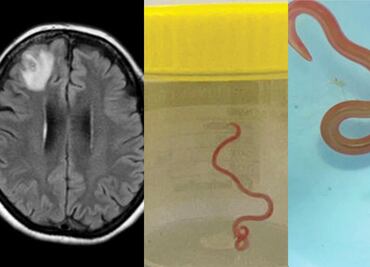

Un grupo de neurocirujanos extrajeron del cerebro de una mujer australiana una lombriz intestinal viva de ocho centímetros